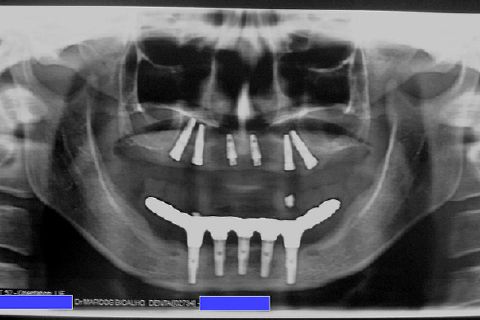

Atualização do caso clínico que já postei, "REABILITAÇÃO EM MAXILA ATRÓFICA COM IMPLANTES", um caso que inclui expansão do rebordo estreito com cinzel e martelo, expansores rosqueáveis, enxerto e instalação dos implantes distais inclinados tangenciando seio maxilar. Inclui esvaziamento do forame nasopalatino e preenchimento com biomaterial para instalação de dois implantes próximos dele. Cirurgia realizada em única sessão, com instalação dos 6 implantes. Para os colegas que não conheceram e/ou esqueceram da apresentação, este é o resumo do caso na fase cirúrgica.http://www.youtube.com/watch?v=BtvexFexRPA&hd=1

FASE PROTÉTICA DA REABILITAÇÃO EM MAXILA ATRÓFICA...incluindo a reabertura, instalação dos minipilares e PTR provisória reembasada sobre os cilindros de proteção.